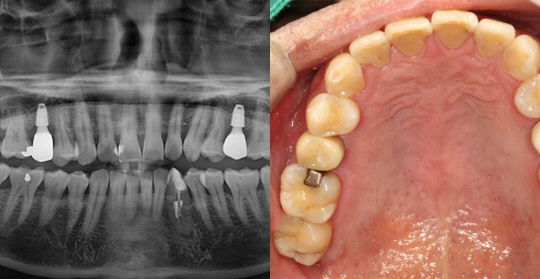

(61세 남 환자)